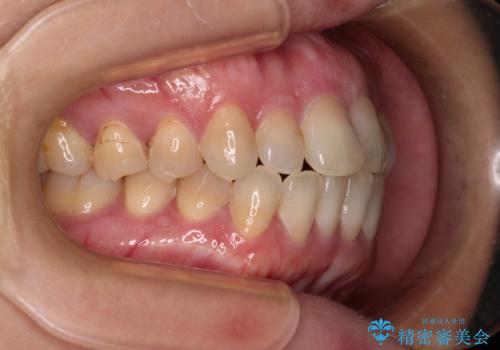

- 前歯のデコボコと口元の突出感を気にして来院された患者様です。

上下前歯がくちばしのように突出していたため、上下左右の第一小臼歯4本を抜歯し、ワイヤー装置にて矯正治療を行うこととしました。

上顎骨に対して下顎骨がやや前方位に位置しているため、歯肉退縮を回避するために下顎前歯をあまり内側に移動させることができない状況でしたが、十分に口元の突出感を改善することができました。